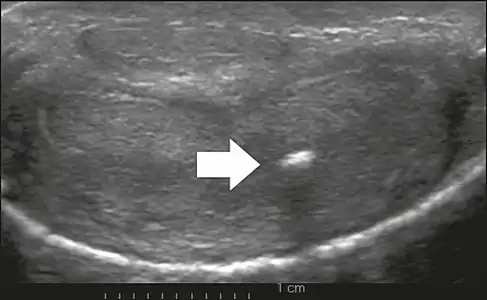

This ultrasound depicts cross sections of the penis at different locations in a patient with Peyronie's disease. The top image shows normal anatomy whereas the bottom image shows scar tissue on the tunica albuginea (penis). The scar tissue is localized and responsible for the hallmark deformities of Peyronie's disease (curvature and narrowing).

On penile ultrasonography, the typical appearance is hyperechoic focal thickening of the tunica albuginea. Due to associated calcifications, the imaging of patients with Peyronie's disease shows acoustic shadowing, as illustrated in figures below. Less common findings, attributed to earlier stages of the disease (still mild fibrosis), are hypoechoic lesions with focal thickening of the paracavernous tissues, echoic focal thickening of the tunica without posterior acoustic shadowing, retractile isoechoic lesions with posterior attenuation of the beam, and focal loss of the continuity of the tunica albuginea.

In the Doppler study, increased flow around the plaques can suggest inflammatory activity and the absence of flow can suggest disease stability. Ultrasound is useful for the identification of lesions and to determine their relationship with the neurovascular bundle. Individuals with Peyronie's disease can present with erectile dysfunction, often related to venous leakage, due to insufficient drainage at the site of the plaque. Although plaques are more common on the dorsum of the penis, they can also be seen on the ventral face, lateral face, or septum.[13]